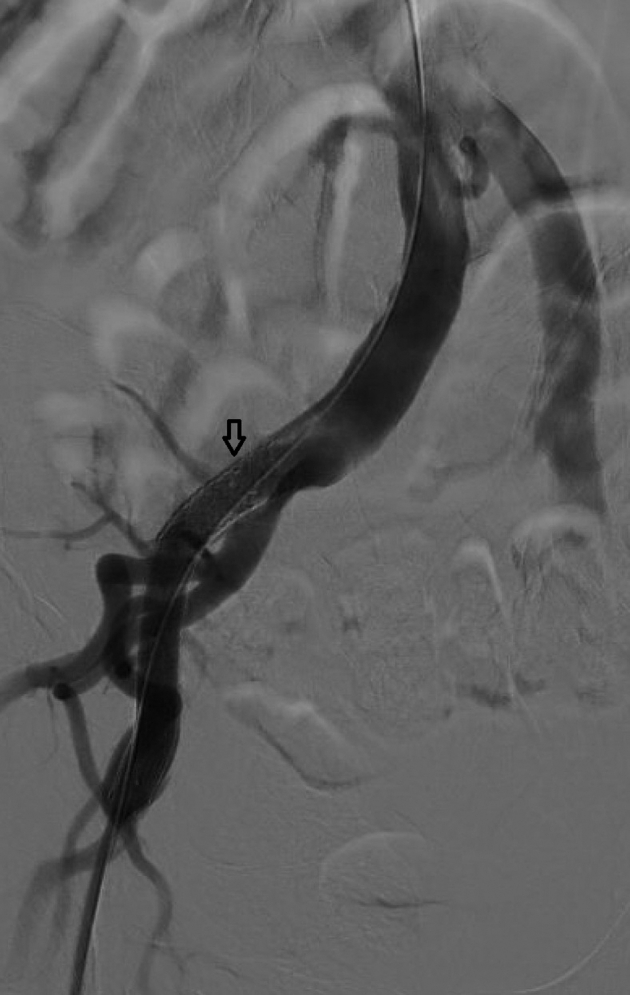

Fig 4.

Initial arteriogram showing lack of flow through the right external iliac artery (EIA).